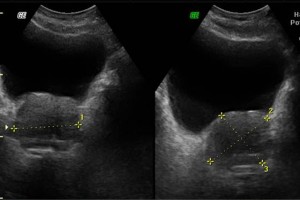

Diplomados en Ultrasonografía